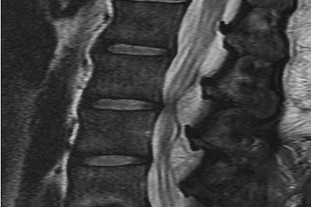

A 65-year-old male presents with classic symptoms of neurogenic claudication. He reports bilateral leg pain and fatigue that worsens with walking but is reliably relieved by leaning forward onto a shopping cart. In the pathogenesis of degenerative lumbar spinal stenosis, which structure is primarily responsible for dynamic central canal compression during spinal extension?

Explanation

In degenerative lumbar spinal stenosis, extension of the spine decreases the sagittal diameter of the canal because the ligamentum flavum buckles inward (shingling), dynamically compressing the thecal sac. Flexion of the spine pulls the ligamentum flavum taut, increasing the available canal space and alleviating neurogenic claudication symptoms. Hypertrophic ligamentum flavum is a major structural contributor to central stenosis.